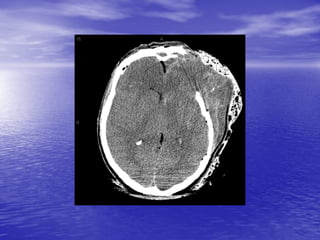

This document discusses the management of intracranial pressure and cerebral edema in neurocritical care patients. It covers topics such as how patients typically present with brain injuries, important caveats in neurological examinations, principles of cerebral resuscitation, mechanisms of primary and secondary brain injury, the pathophysiology over time, imaging techniques including CT scans and MRI, monitoring techniques like intracranial pressure monitoring, and treatment approaches like the use of hyperosmolar therapy with mannitol or hypertonic saline. The goal is to prevent secondary brain injury after the initial primary injury occurs.